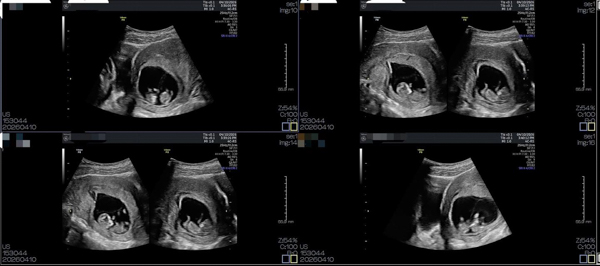

於7周超音波檢查發現有雙胞胎妊娠🧐

目前兩位寶寶都充滿活力💖

但是植入1顆胚胎仍然有1~2%機率會有同卵雙胞胎發生

同卵雙胞胎若是單ㄧ羊膜腔的風險將會更高